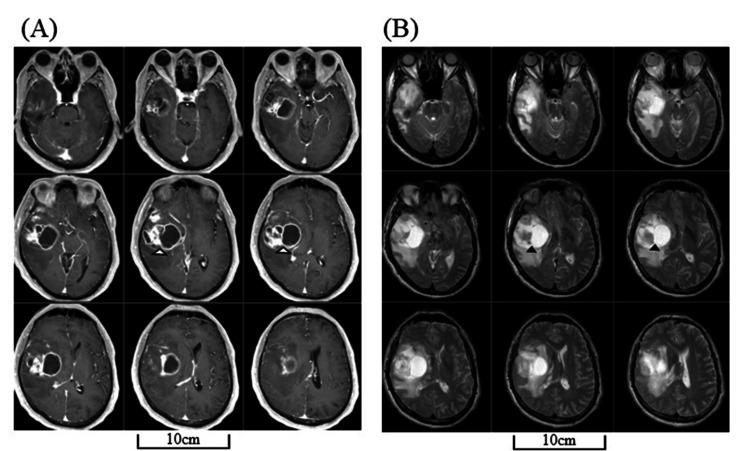

Dysprosody affects rhythm and intonation in speech, resulting in the impairment of emotional or attitude expression, and usually presents as a negative symptom resulting in a monotonous tone. We herein report a rare case of recurrent glioblastoma (GBM) with dysprosody featuring sing-song speech. A 68-year-old man, formerly left-handed, with right temporal GBM underwent gross total resection. After chemoradiation therapy, he was discharged without any deficits. Nineteen months later, the patient exhibited recurrence and presented a peculiar way of speaking with excessive melodic intonation. A head magnetic resonance imaging revealed new enhanced lesions in the residual right temporal lobe and the splenium of the corpus callosum with a massive surrounding T2-high area. The case highlights the bilateral hemispheric network underlying prosody and the compensatory failure caused by tumor progression and connectivity disruption. This first account of sing-song dysprosody in a GBM patient underscores the complexity of the language network and the need for further case accumulation to elucidate the pathophysiology of such rare presentations.

摘要

韵律障碍会影响言语的节奏和语调,导致情感或态度表达受损,通常表现为一种消极症状,致使语调单调。我们在此报告一例罕见的复发性胶质母细胞瘤(GBM)伴韵律障碍,其特征为吟诗样言语。一名68岁男性,既往左利手,患有右侧颞叶GBM,接受了肿瘤全切术。放化疗后,他出院时无任何神经功能缺损。19个月后,患者出现复发,并表现出一种奇特的说话方式,语调过度富有旋律。头部磁共振成像显示右侧颞叶残余部分及胼胝体压部有新的强化病灶,周围有大片T2高信号区。该病例突出了韵律背后的双侧半球网络以及肿瘤进展和连接中断所导致的代偿失败。这是首次报道GBM患者出现吟诗样韵律障碍,强调了语言网络的复杂性以及需要进一步积累病例以阐明此类罕见表现的病理生理学。